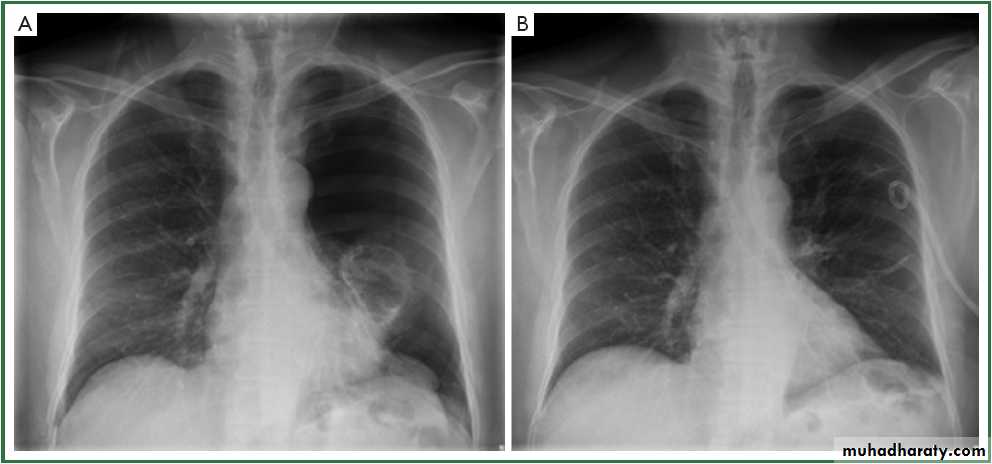

Pneumothorax

A: before treatmentB: after treatment